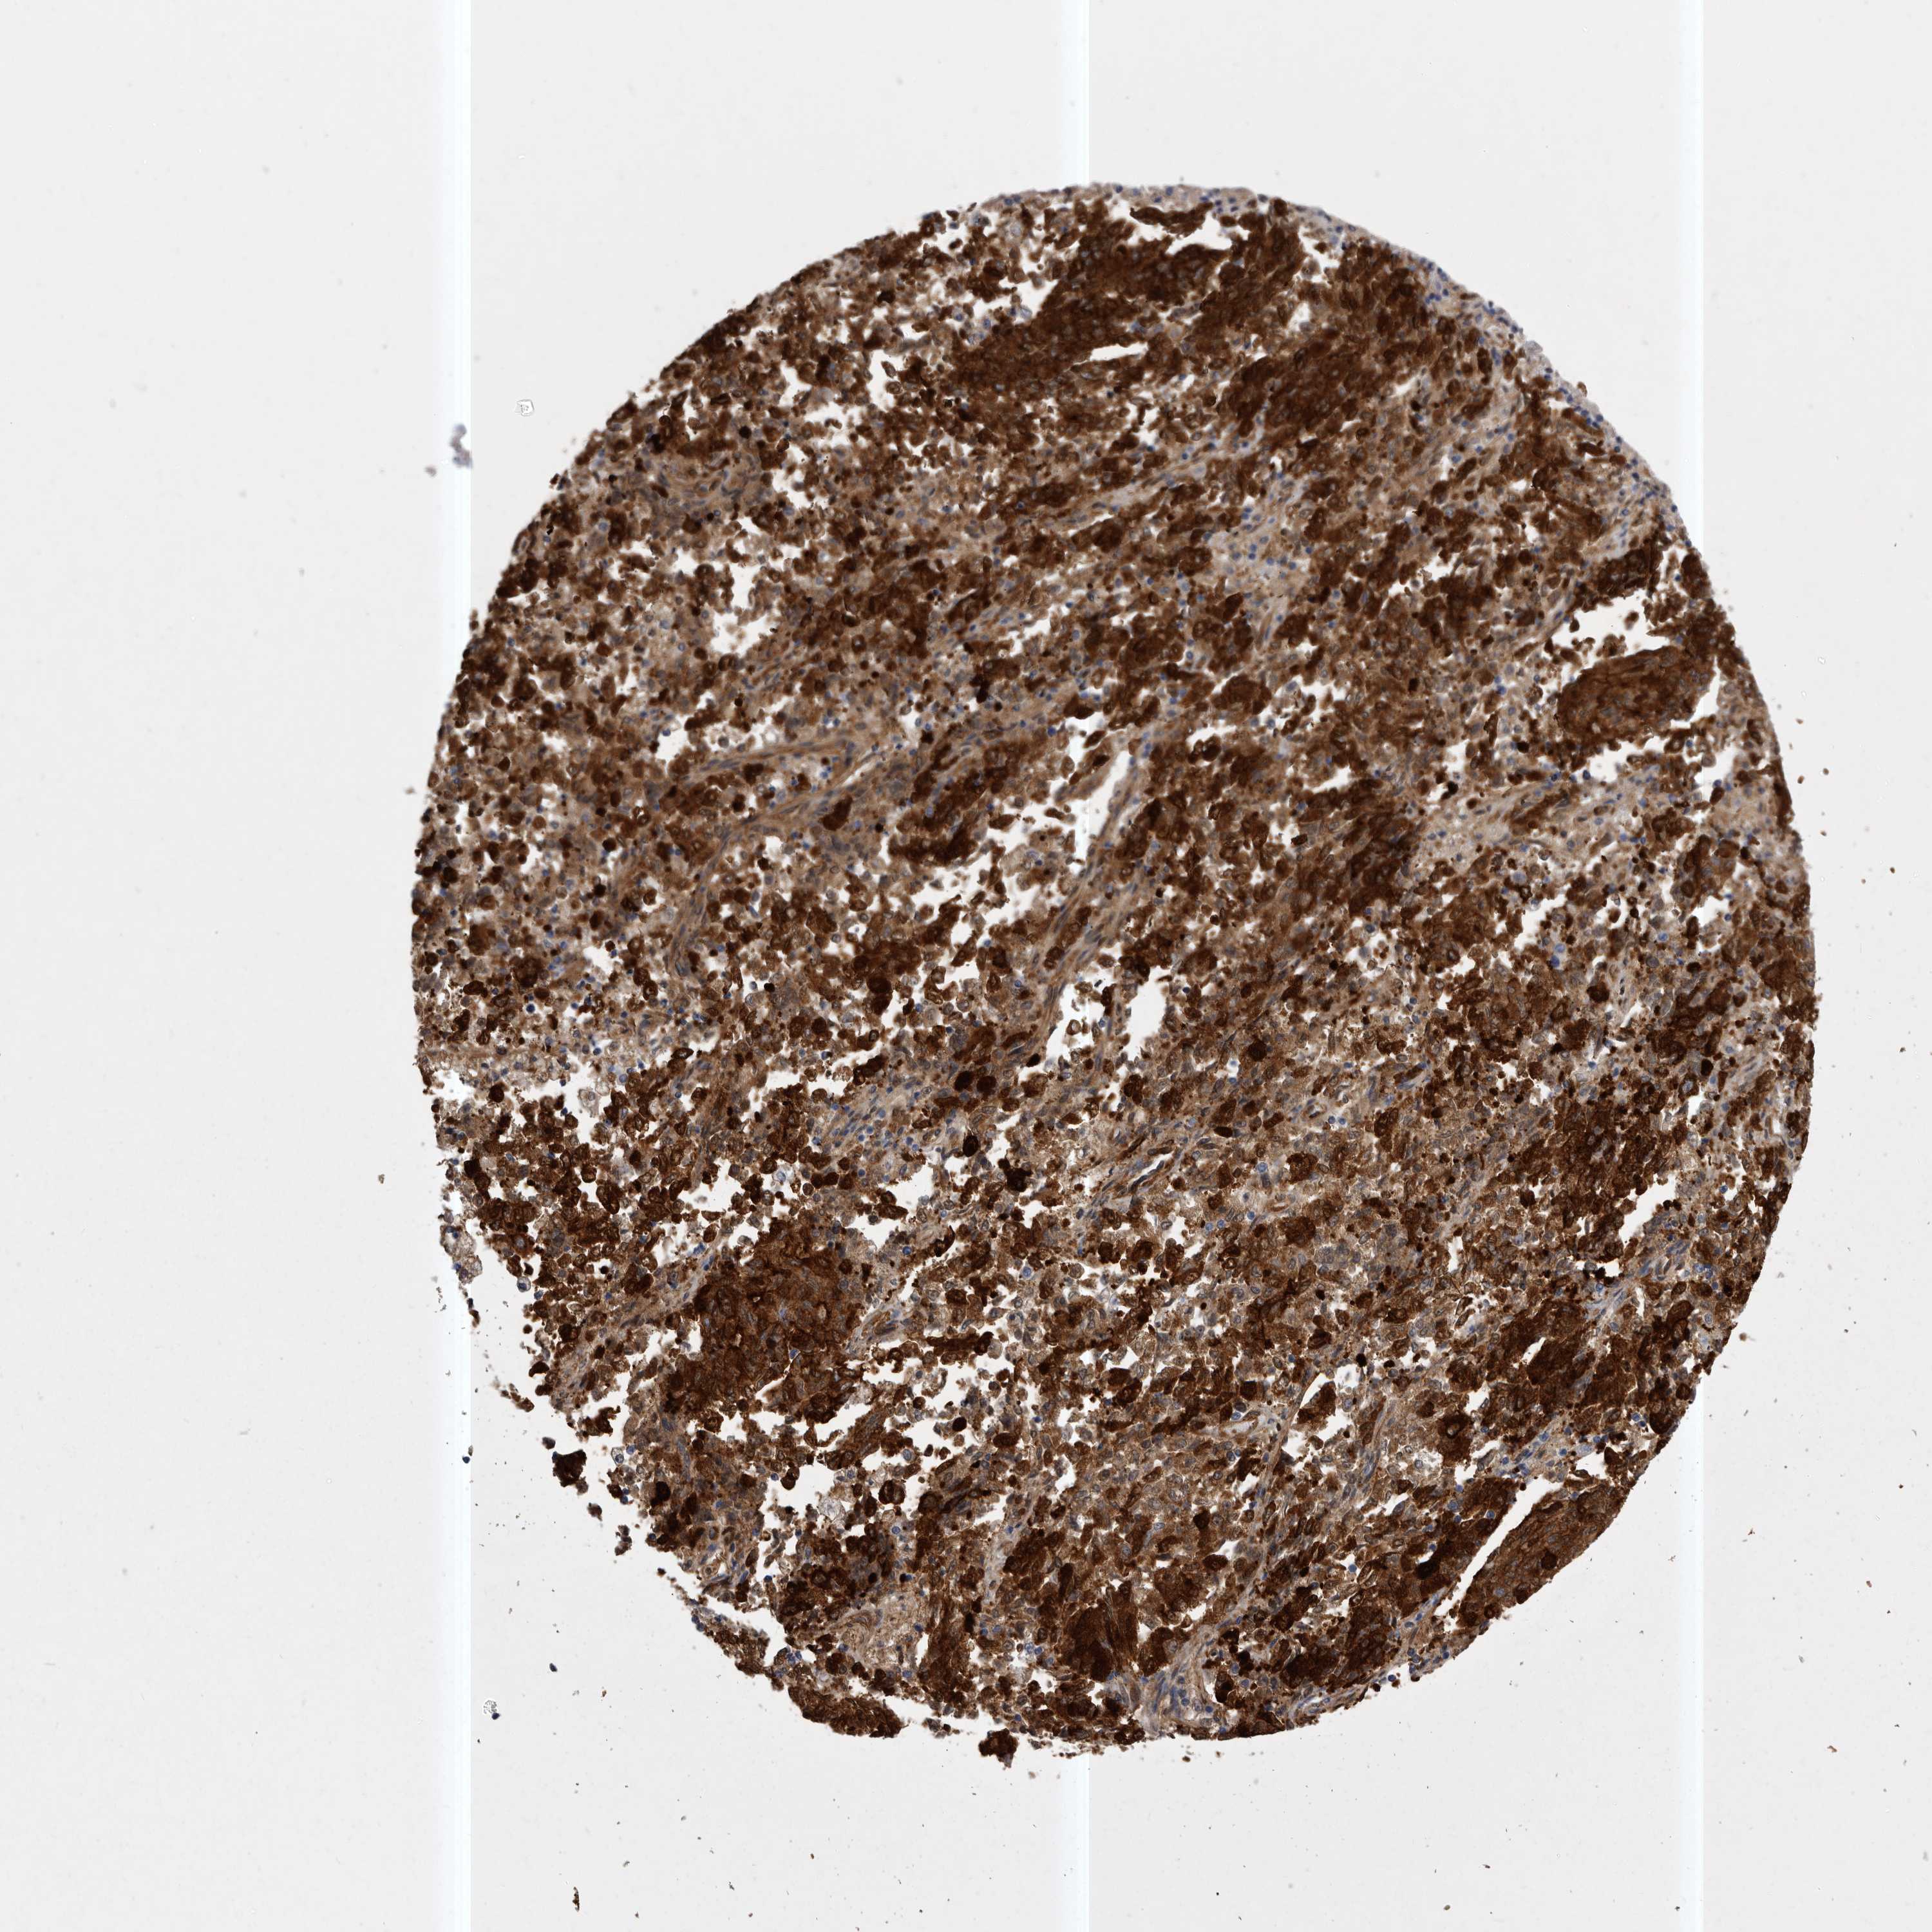

ENDOMETRIAL CANCER - Protein expressioni

A mouse-over function shows sample information and annotation data. Click on an image to view it in a full screen mode. Samples can be filtered based on level of antibody staining by selecting one or several of the following categories: high, medium, low and not detected. The assay and annotation is described here.

Note that samples used for immunohistochemistry by the Human Protein Atlas do not correspond to samples in the TCGA dataset.

Antibody stainingi

Antibody staining in the annotated cell types in the current human tissue is reported as not detected, low, medium, or high, based on conventional immunohistochemistry profiling in selected tissues. This score is based on the combination of the staining intensity and fraction of stained cells.

Each image is clickable and will lead to virtual microscopy that enables deeper exploration of all samples and also displays staining intensity scores, fraction scores and subcellular localization as well as patient and tissue information for each sample.

Antibody HPA028448

Antibody HPA028696

Staining

High

Medium

Low

Not detected

Intensity

Strong

Moderate

Weak

Negative

Quantity

>75%

75%-25%

<25%

None

Location

Nuclear

Cytoplasmic/membranous

Cytoplasmic/membranous,nuclear

Adenocarcinoma, NOS

Adenocarcinoma, metastatic, NOS